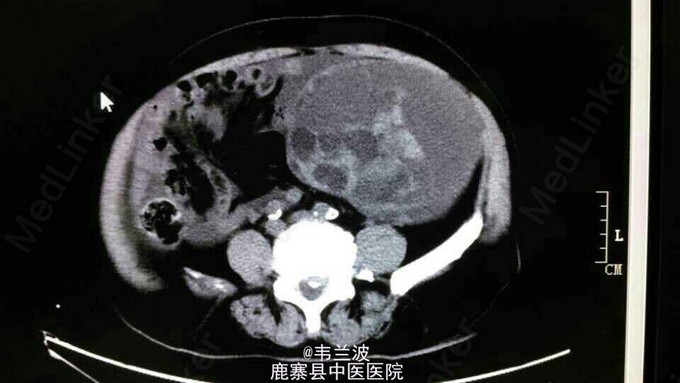

腹部肿块

中老年妇女,发现腹部包块半年。其他病史不详,未作增强。大家讨论一下什么疾病可能性大。